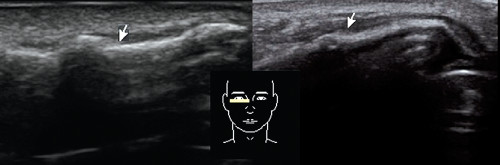

Ультразвуковое исследование носа: стойкие изменения формы носа после травмы. Стрелка на изображении указывает на область, где произошло сращивание переломов, а датчик установлен поперечно на правом скате носа.

В процессе процедуры возможно точно определить увеличение полипов, образование кист в области носовых пазух, их повреждения в результате травмы, а также острое состояние при осложнениях воспалительных процессов в пазухах и травмах.

Исследование носа с использованием ультразвука: нормальные показатели и признаки переломов.